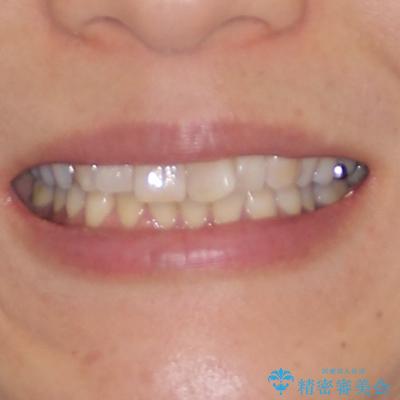

- 前歯のデコボコと上下正中のずれを気にして来院された患者様です。

下顎骨が骨格的にずれがあったため、しっかりと正中を合わせるとなるとワイヤー矯正が必要でしたが、マウスピース矯正を希望されたため、極力正中を合わせることを目標に、インビザラインにて矯正治療を行うこととしました。